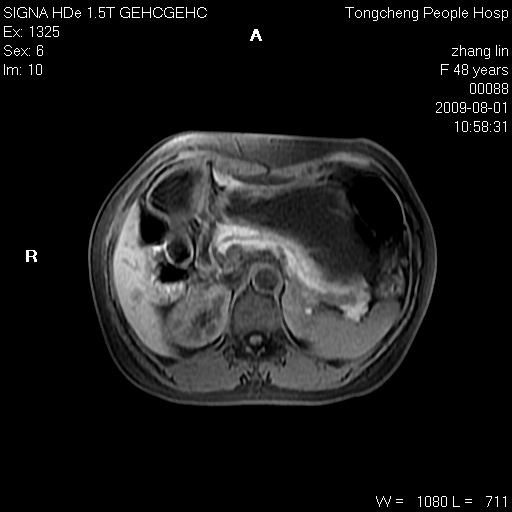

女,48岁。健康体检,彩超发现右肾占位性病变。平素健康。

临床诊断:右肾占位性病变,性质待定(囊肿?肿瘤?)。

上中腹部mr平扫+增强扫描,图像如下:

右肾上极见一类圆形病灶,t1wi呈等信号t2wi呈等高混杂信号,三期增强无强化,边界清---考虑囊肿出血。

同反相位均表现为等信号,病变无强化,考虑含蛋白的囊肿可能,弥散加权相或许有些帮助,